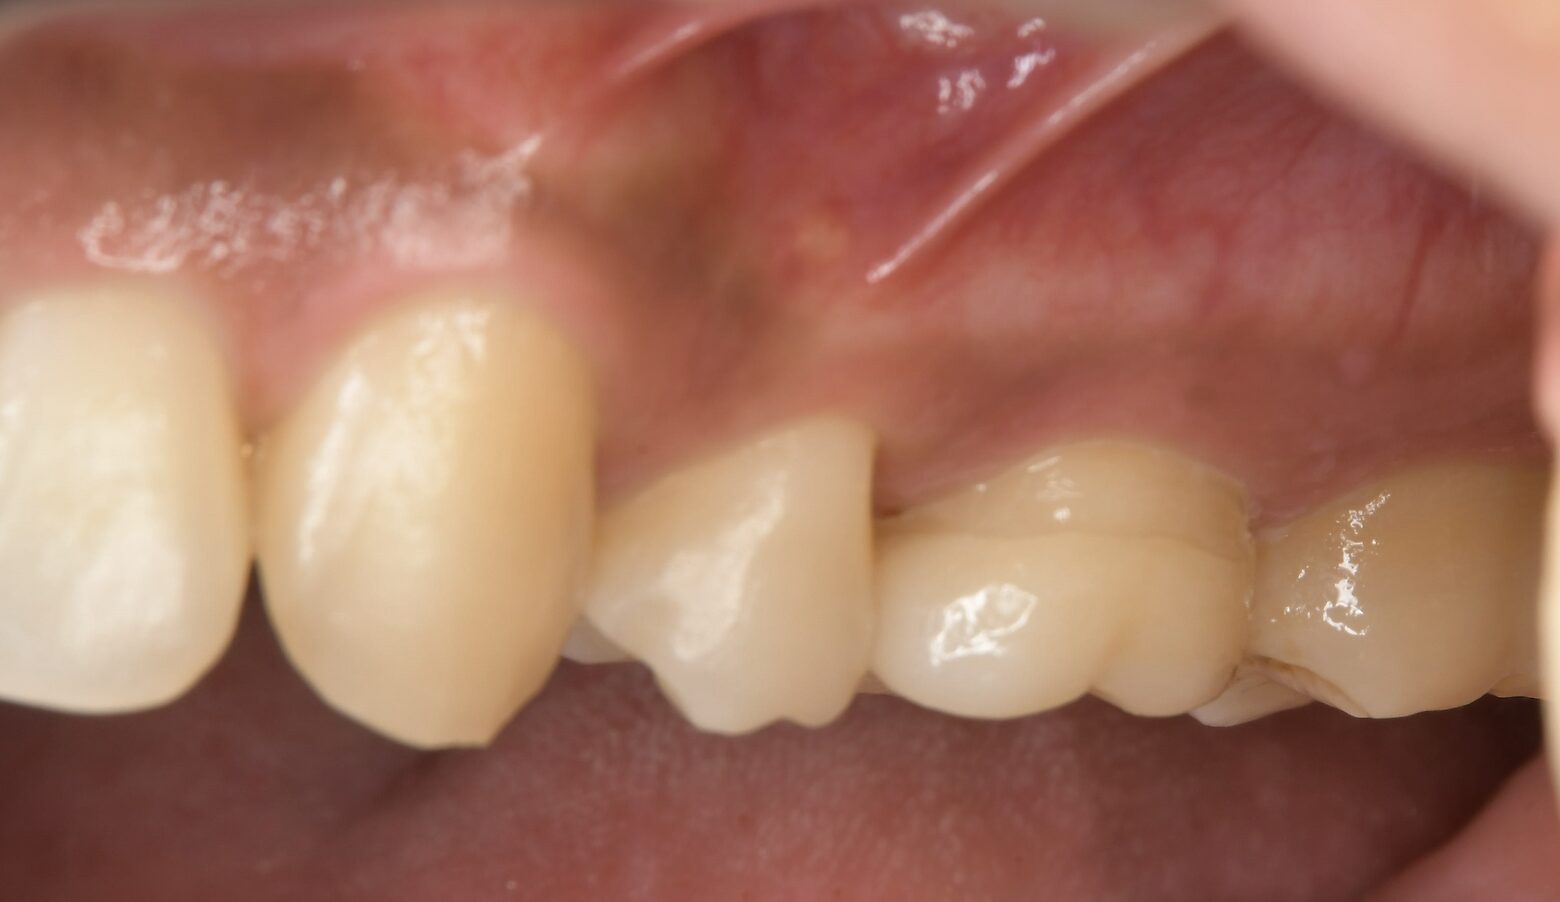

症例 上顎第一大臼歯抜髄処置 2025.10.02 【主訴】 上顎第一大臼歯部の自発痛出現にて、歯内療法専門医受診希望 【背景】 上顎第一大臼歯部に自発痛出現し、根管形態の複雑さから、歯内療法専門医にて治療を示唆 診査診断後、通報に従い、一回の処置で歯内療法及び支台歯築造まで終了し、 仮歯にて1週間ほど経過観察し、セラミック修復に至る 治療前 治療後 セラミック咬合面 セラミック頬側面 【考察】 元々、食いしばり傾向が強く認められる患者であり、メタルインレーにて咬合面をほぼ覆う形態で修復されていた この場合、咬合力コントロールされていない症例では、歯にヒビ(クラック)が生じ、噛むと痛いという訴えや、 神経に達する症状が突然出現するケースも散見される 神経が温存される症例でも、全体的にクラウン形態で修復することが望ましい 【治療回数】 歯内療法 1回 歯冠修復 2回 【治療担当医】 歯内療法 野田哲朗 歯冠修復 白土 州 この記事のタイトルとURLをコピーする